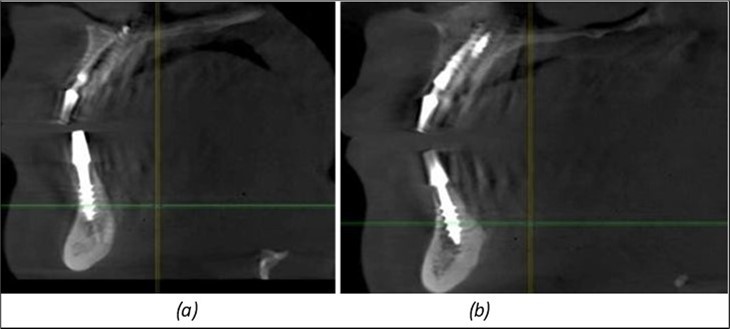

A total of 11 implants is placed in the maxilla, including compressive TPG implants with a polished surface in the maxillary-sphenoid fusion area (Figure 3, Figure 9). Similarly, in the anterior region, final fixation is achieved in the nasal cortex, and BCS corticobasal implants are added in areas with massive bone loss in the frontal region (Figure 3, Figure 8, Figure 11). Additionally, in the palatal sinus cortical area, with the aim of avoiding the addition and sinus lift zone where the second cortical bone no longer exists, 3 implants are placed, 2 in quadrant 1 and 1 in quadrant 2 (Figure 3, Figure 8). Through the Caldwell-Luc sinus lift procedure, the sinus cortical bone is displaced to allow the placement of the graft material and elevation of the sinus membrane. This sinus cortical is no longer recreated at the junction of the graft material and mucosa-sinus membrane, making it impossible to place a corticobasal implant, which relies on the second cortical bone. In the distal mandibular area, after the removal of two stage implants due to massive destruction in quadrant 3, implant placement distal to the mylohyoid line is not possible, as in quadrant 4 (Figure 10). A re-intervention occurs after 5 months to stabilize the area (Figure 12, Figure 14). Also, at the moment of fixation, the tip of one implant fractures, and the decision is made to leave it in place due to regional bone destruction, in order to avoid enlarging the bone defect.

Figure 12.Implants fixed distally in quadrant 4 with fixation at the level of the mylohyoid line: (a) The most distal implant fixed in unaffected bone from the previous restoration; (b) The implant fixed in the area where the two stage implant was removed.